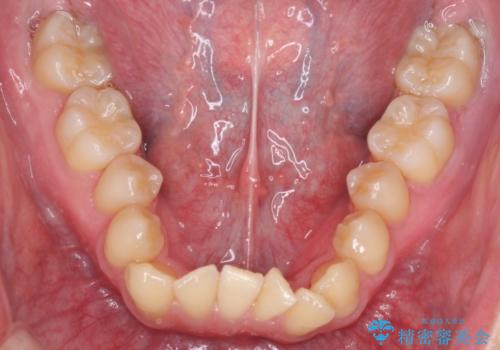

- 前歯のがたつきが気になるとのことで来院されました。

骨格的なところと、上下の歯の大きさのことを考慮して、下の前歯を1本抜歯し、インビザラインにて矯正治療することとなりました。